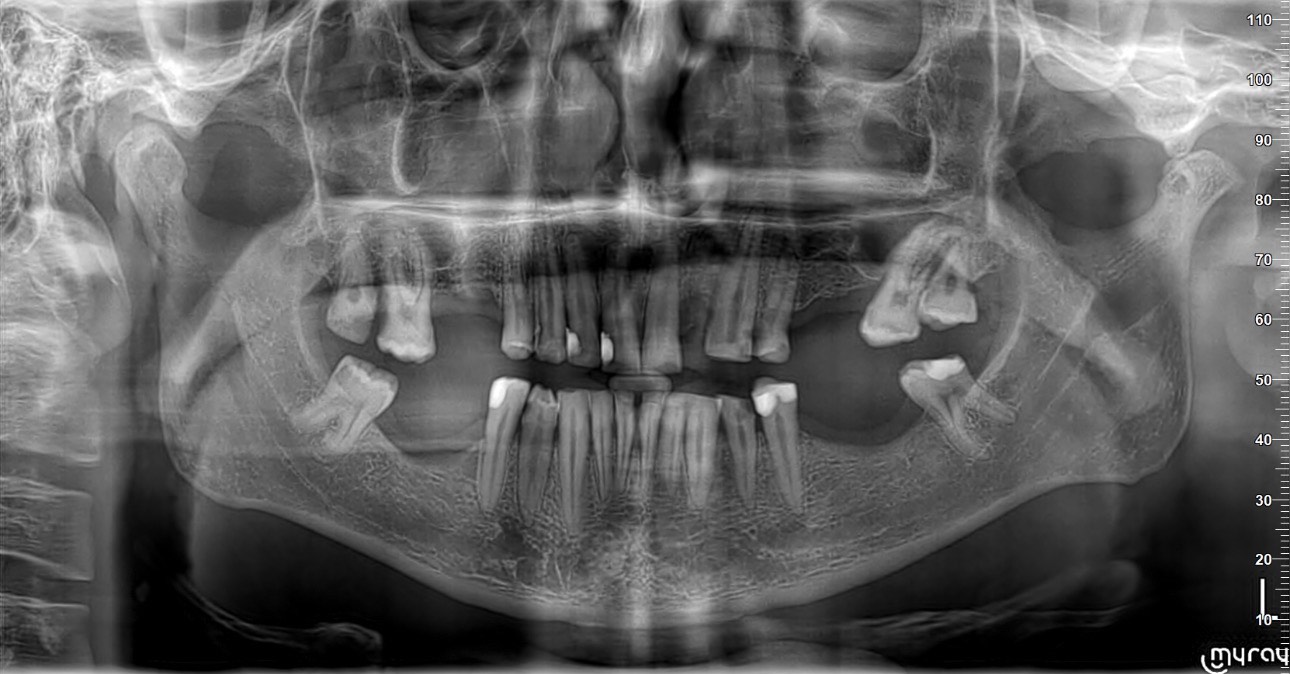

Përpara planifikimit përfundimtar, u krye një ekzaminim i plotë diagnostik, duke përfshirë:

• Ekzaminim klinik të detajuar • Imazheri 2D • 3D Scanner intraoral, për analizë precize të okluzionit, formës dentare dhe marrëdhënieve skeletike.

Kjo fazë ishte thelbësore për të ndërtuar një plan trajtimi të sigurt dhe të personalizuar.